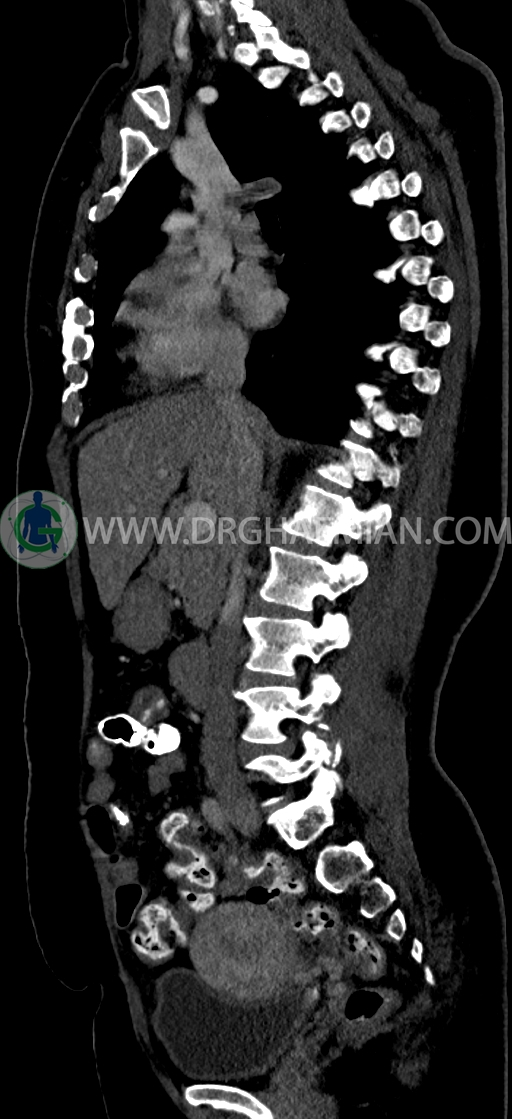

در سي تي اسکن اسپيرال ريه و مدياستن-شکم و لگن با کنتراست خوراکی و وريدی (مولتي ديدکتور 16 با مقاطع ظريف و بازسازي هاي ساژيتال و کرونال) :

-فيبروم اينترامورال- ساب سروزال به سايز 35mm در قدام فوندوس با اثر فشاري بر ديواره فوقاني مثانه

–Bridging osteophyte در مهره هاي توراسيک مطرح کننده DISH همراه با کيفوز مشهود است.

–lumbosacral transitional vertebrae

-هرني سوپرا امبليکال با ديفکت به سايز 10mm حاوي چربي و هرني امبليکال با ديفکت به سايز 7mm حاوي چربي مشهود است.